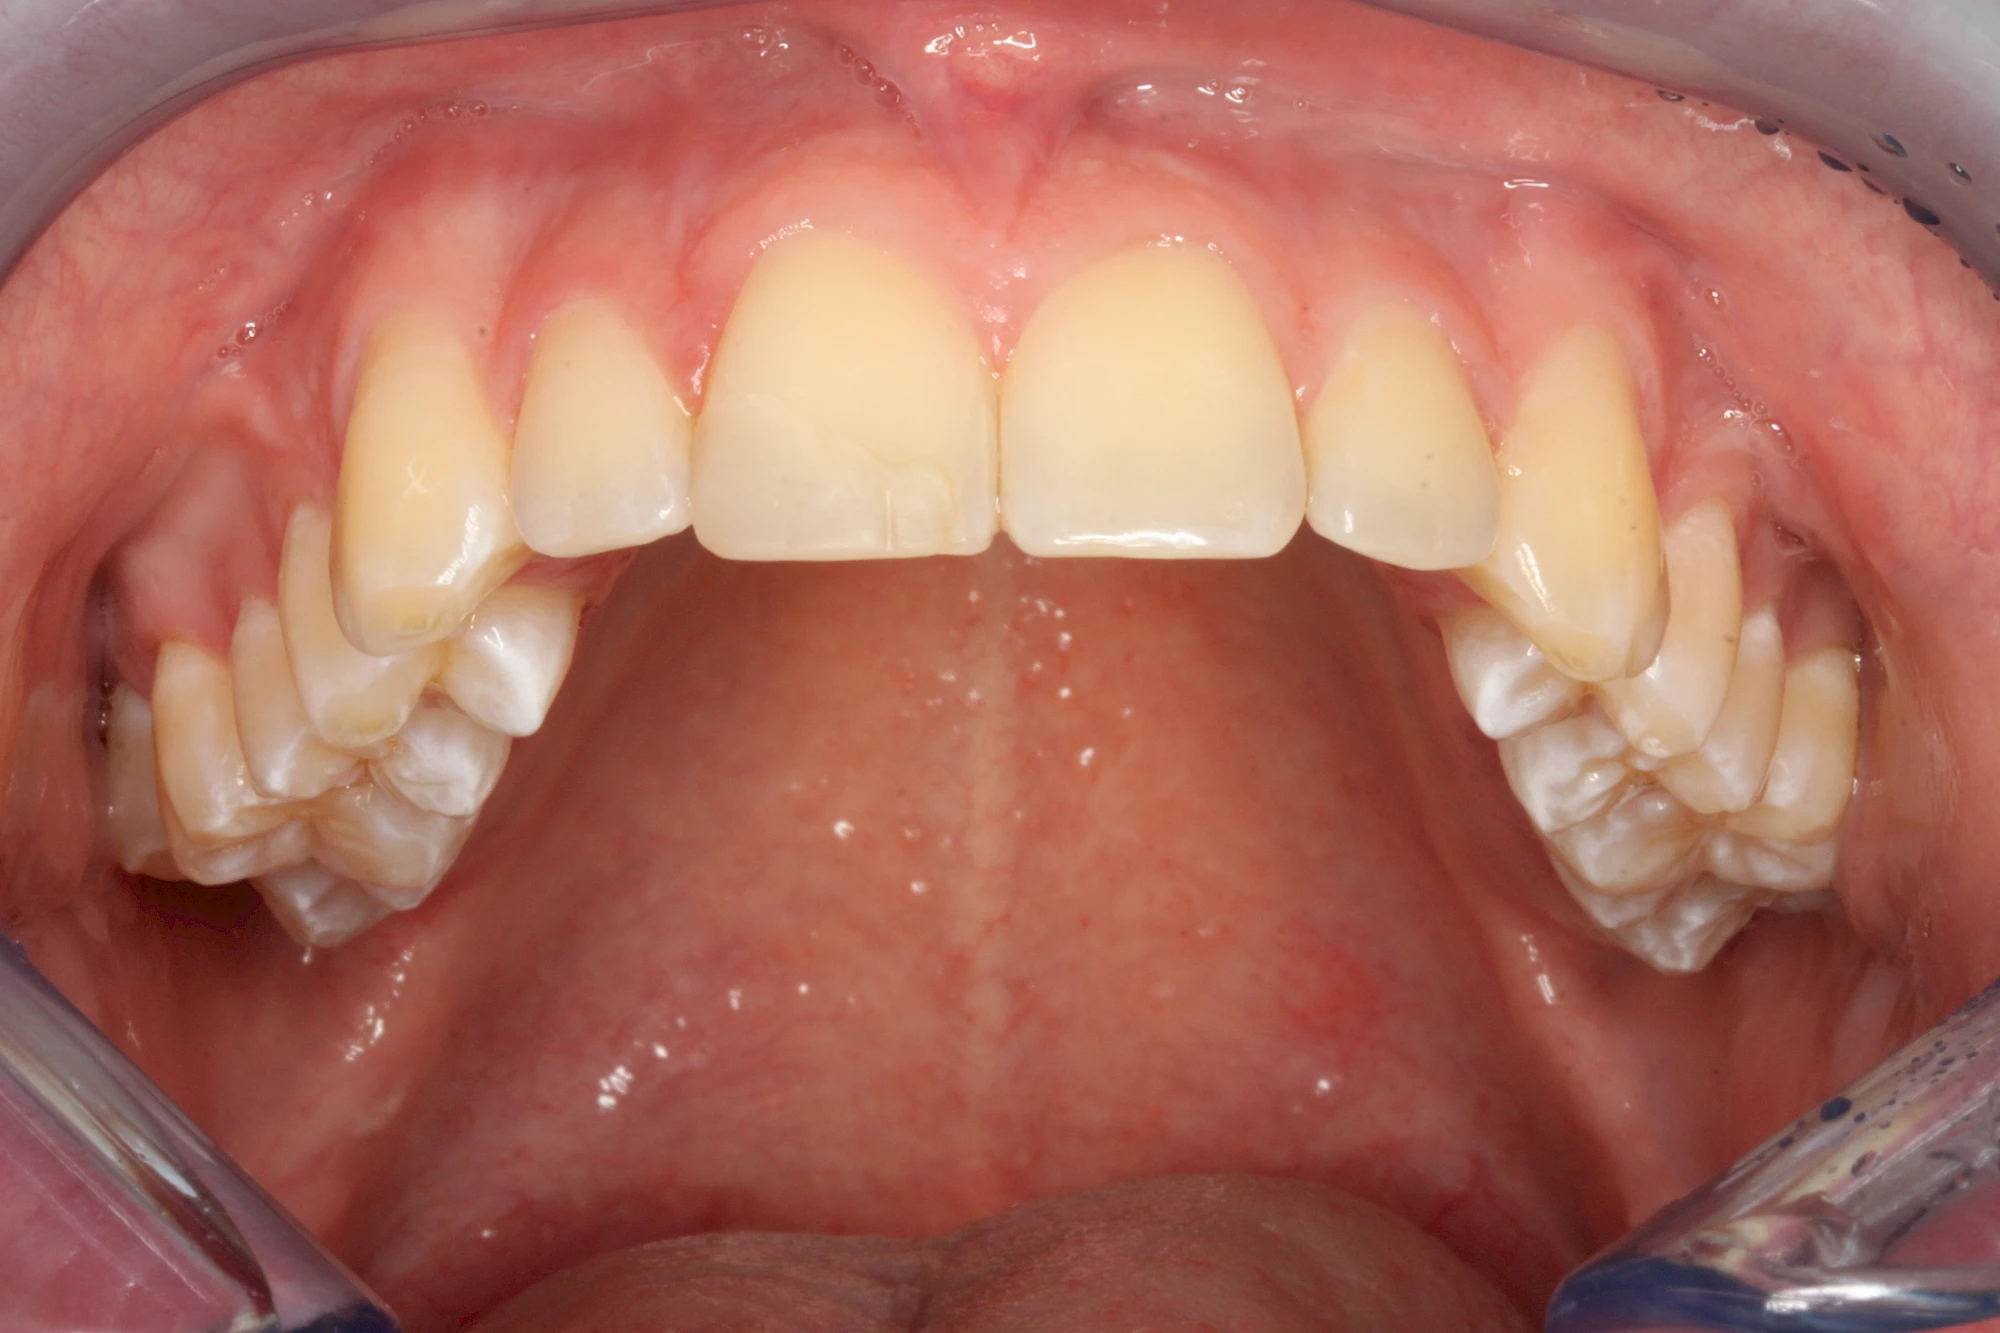

Gerade bei Kindern und Jugendlichen werden zunehmend häufiger bräunliche Verfärbungen mitunter auch mit Formveränderungen (die Oberfläche ist rauh oder zerklüftet) der Zähne beobachtet. Meist sind Schneidezähne oder Backenzähne betroffen. Dies könnte ein Hinweis auf sogenannte Kreidezähne (MIH: Molaren-Inzisiven-Hypomineralisation) sein.

Bräunliche Verfärbung